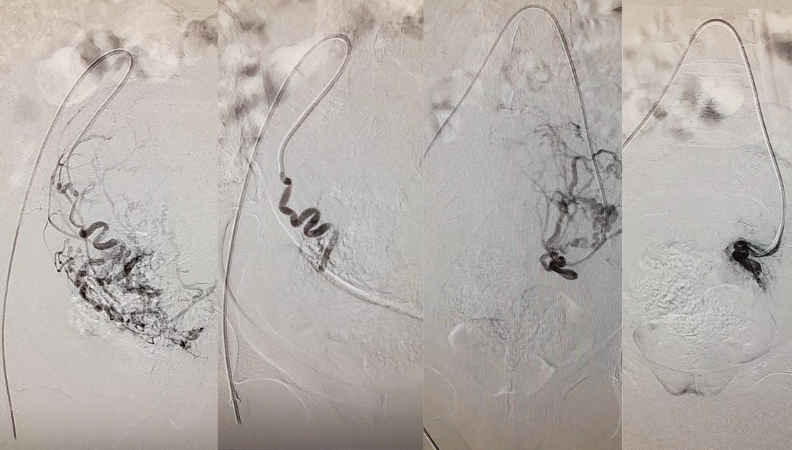

Brain Aneurysm Coiling

Brain aneurysm coiling is a minimally invasive procedure that uses tiny coils to block blood flow into an aneurysm, preventing rupture and stroke